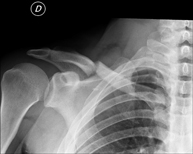

Tècnica que usa els raigs X a través de la qual s'obtenen imatges de l'estern per al seu estudi - RX Clavícules

Tècnica que usa els raigs X a través de la qual s'obtenen imatges de les clavícules per al seu estudi - RX Parilla costal

- RX Extremitats

Tècnica que usa els raigs X a través de la qual s'obtenen imatges de l'interior de les extremitats per al seu estudi, especialment dels ossos. Indicacions: traumatisme, infeccions articulars. - RX Artrografia